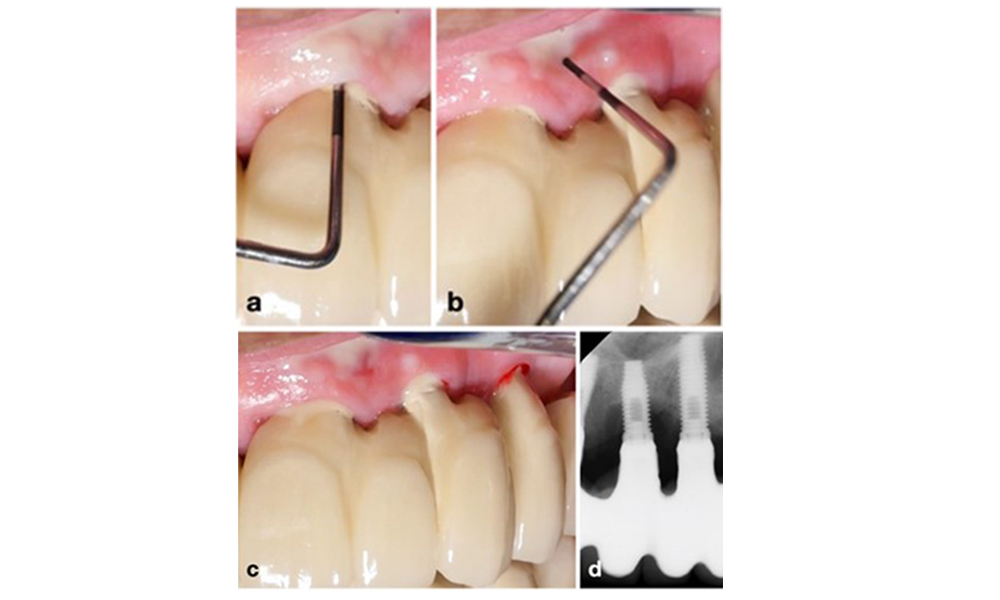

Peri-implantitis is identified by (1) signs of inflammation similar to mucositis, (2) radiographic evidence of bone loss after initial healing and (3) an increase in probing depth compared to measurements taken shortly after placing the prosthetic reconstruction (figure 2). In the absence of previous radiographs, radiographic bone level of ≥ 3 mm along with bleeding on probing and probing depths ≥ 6 mm, indicates peri‐implantitis.

The expected bone loss after initial healing attributed to marginal bone remodelling, varies based on factors such as the implant system or type. For instance, 1–2 mm bone loss is generally considered “normal” for bone level implants with an external connection (figure 2d, implant in position 23).